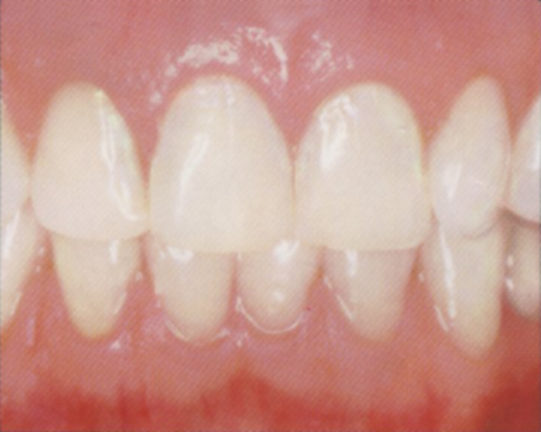

Zdravé dásně, obr. 1

- mají bledě růžovou barvu

- nekrvácí

- okraj dásně pevně obepíná zuby